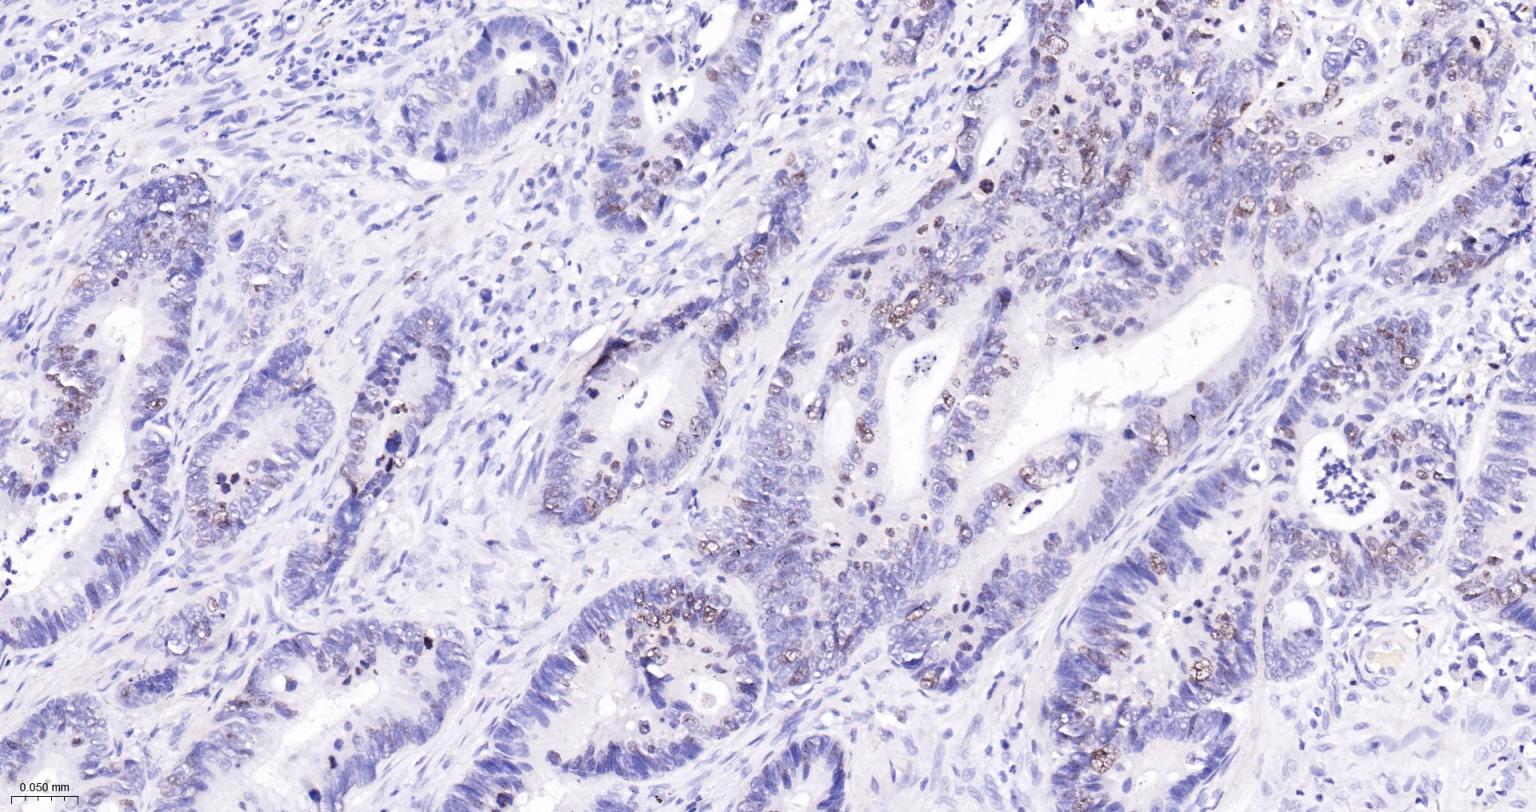

IHC-PHuman, RatMouse1:100-500

Ki67与PCNA一样,为细胞增殖的一种标记,在细胞凋亡中S、G2 、M期均有表达,G0期缺如。

Ki-67增殖指数高低与许多肿瘤的分化程度、浸润、转移以及预后密切相关,因此被广泛作为各种恶性肿瘤的必检项目之一。

Ki67 antigen is the prototypic cell cycle related nuclear protein, expressed by proliferating cells in all phases of the active cell cycle (G1, S, G2 and M phase). It is absent in resting (G0) cells. Ki67 antibodies are useful in establishing the cell growing fraction in neoplasms (immunohistochemically quantified by determining the number of Ki67 positive cells among the total number of resting cells = Ki67 index). In neoplastic tissues the prognostic value is comparable to the tritiated thymidine labelling index. The correlation between low Ki67 index and histologically low grade tumours is strong. Ki67 is routinely used as a neuronal marker of cell cycling and proliferation.